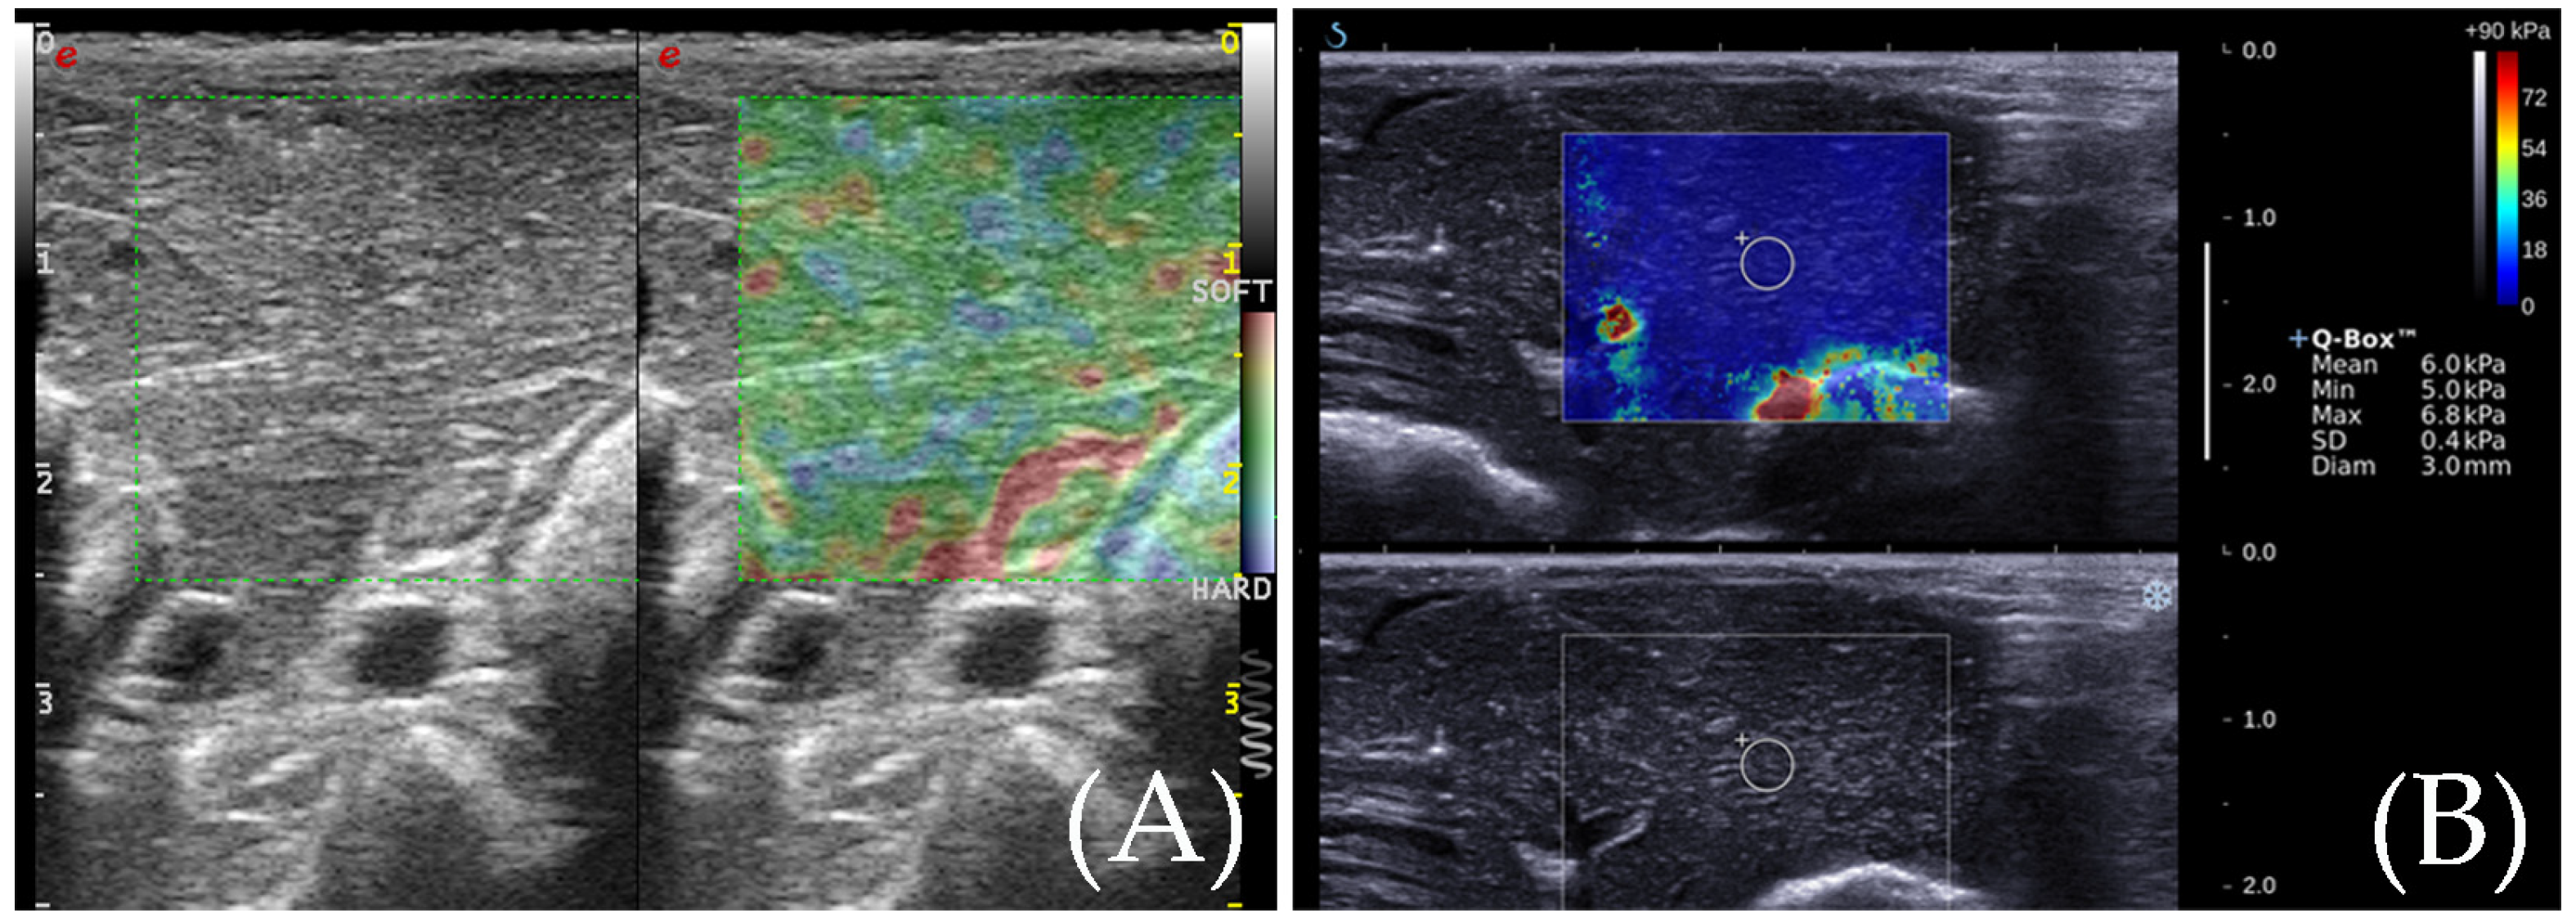

RTE

SWE

3.2. RTE for the Detection of the Ablation Zone

3.3. SWE for the Detection of the Ablation Zone